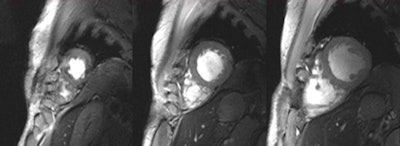

Set of six (top and bottom) 2D CINE FLASH images of the beating human heart derived at systole from a series of 12 short-axis views ranging from the apex to the base of the heart (in-plane resolution [1 x 1] mm2, slice thickness of 4 mm, acceleration factor = 2, GRAPPA). A 2D 16-channel transmit/receive radiofrequency coil array was used for signal transmission and reception.6 The images illustrate that a rather uniform intensity distribution was obtained across the entire heart.6Admittedly, the reports put forward by numerous pioneers and early clinical adopters are so far largely anecdotal. It is a fractal pattern, though, and a consistent story is starting to emerge -- a story worth following since its clinical implications feed into a broad spectrum of neurology, neuroscience, neuroradiology, radiology, cardiology, and other fields of clinical research. This story includes a chapter that comprises around 150 abstracts presented at the recent 20th annual meeting of the International Society of MR in Medicine (ISMRM) held in Melbourne, Australia, and more than 100 clinical research papers published since 2010.

It is no secret that the feasibility of 7-tesla MRI is not limited to the brain, but also can be beneficial for musculoskeletal and cardiac imaging. The requirements of cardiac MR at 7 tesla inspired recent advances in multichannel radiofrequency (RF) coil technology. This includes the move from cardiac optimized RF coils equipped with four transmit/receive channels only to 16 TX/RX channels configurations,6 and even 32 TX/RX channel versions.7

It has been shown that a larger number of elements, in conjunction with a 2D RF coil-array design, can improve image quality, as well as accelerated imaging performance.8 All these efforts culminated in images of the beating heart with a spatial resolution that is by an order of magnitude superior to that routinely available at 1.5 tesla.

These improvements offer detailed insights into cardiac anatomy and might provide means for a better understanding of the myocardial microstructure. Recognition of the benefits of the many channel RF coil configurations should help to eventually lead to a 7-tesla body RF coil design, though this is, for the moment, merely a vision. It is nonetheless a vision that offers the potential to inspire a further push toward body imaging at 7 tesla.